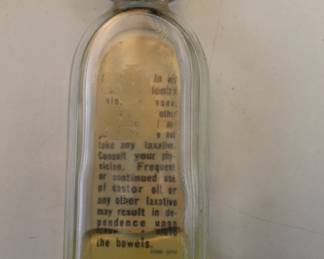

1117 - Vintage Medicine Bottles and Jars